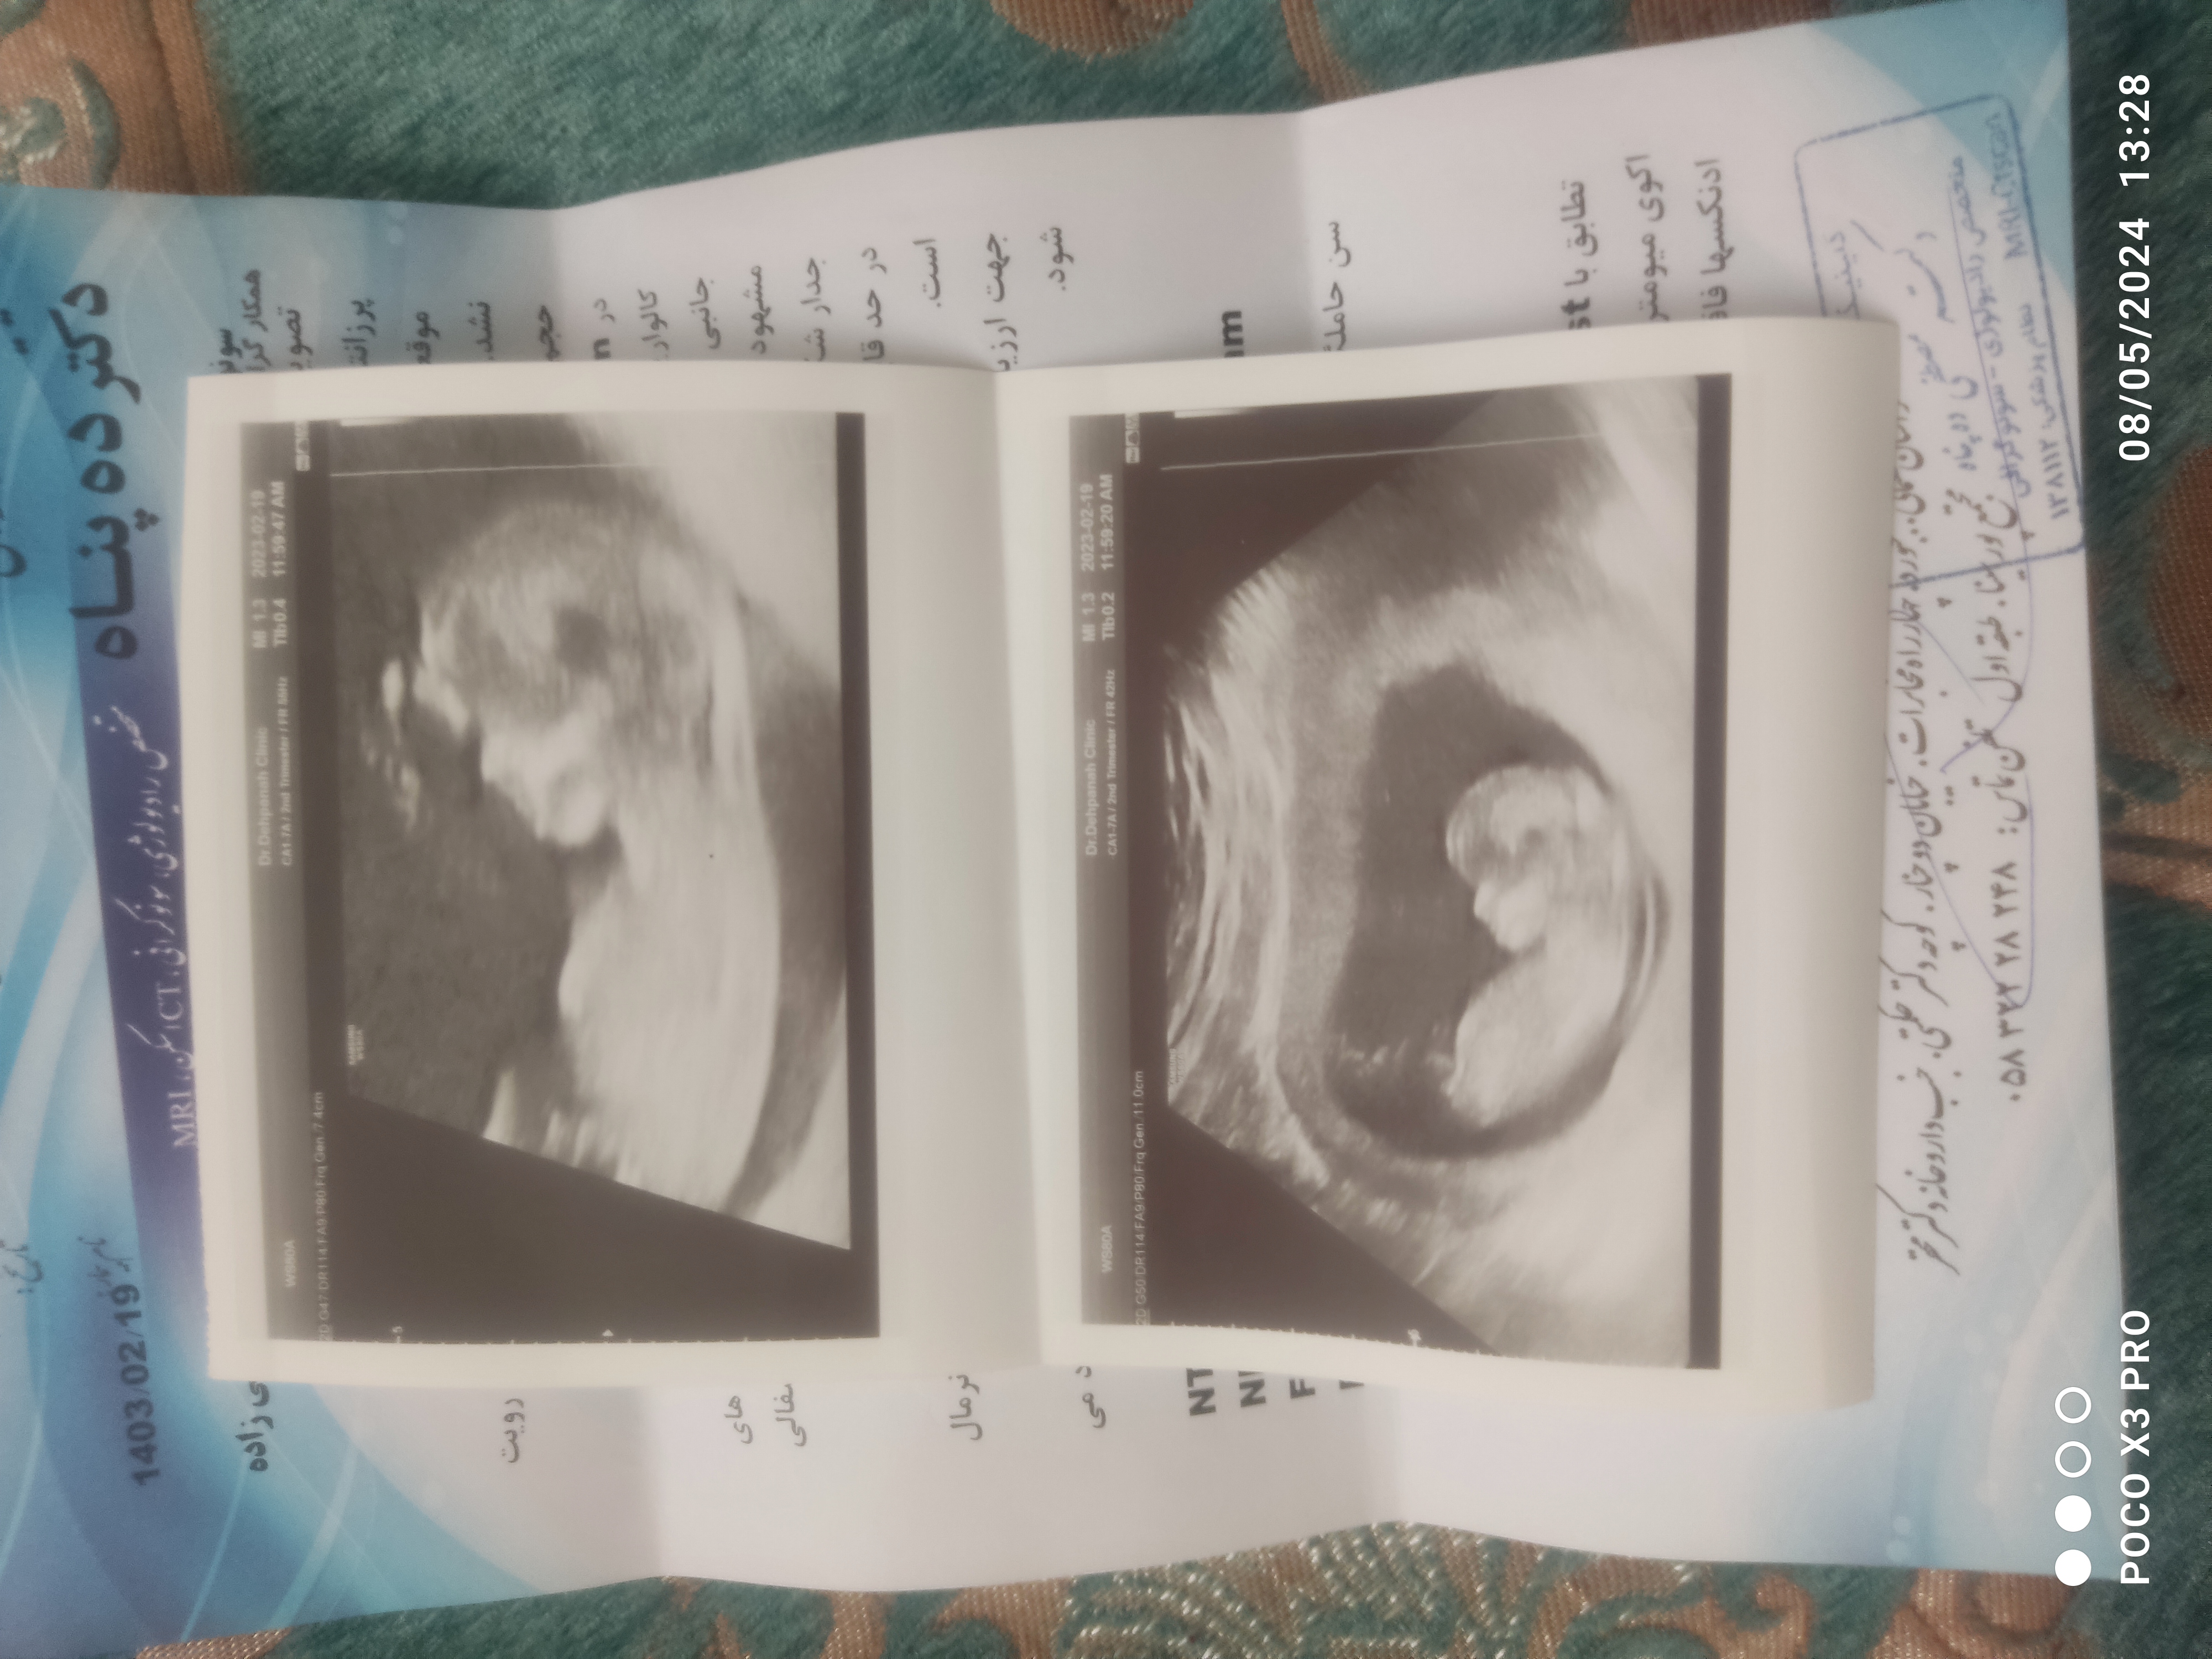

سونو ان تی

بیاین جنسیت حدس بزنین

به نظرت عدد nt طبیعیه

به نظرم دختر

اتفاقا دکتر خودشم تو برگه سونو احتمال دختر داده ولی چیزی بهم نگفت

به پسر میخوره. ان تی خوبه. جواب آزمایشتون هم اومده؟